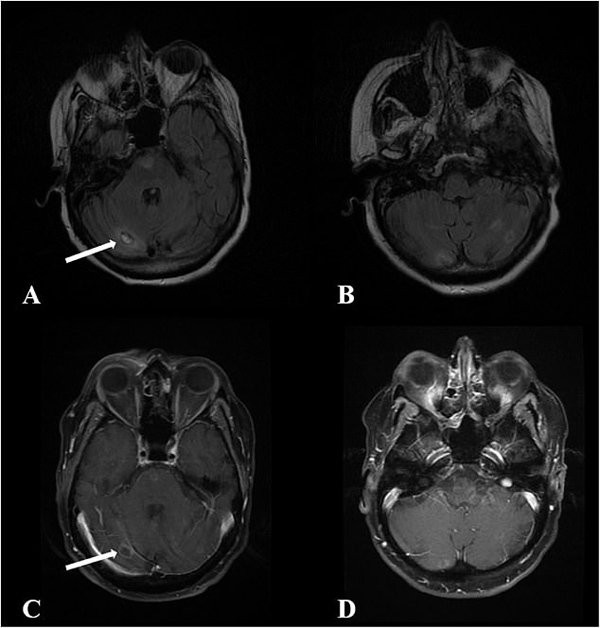

Một lần khác, bà đến bệnh viện ở Seattle và bỗng nhiên lên cơn động kinh co giật, mất đi nhận thức dù trước đó hoàn toàn tỉnh táo. Nhận ra có điều không ổn, các bác sĩ tại đây đã tiến hành chụp CT. Hình ảnh não của bà được nhìn thấy trên tấm phim nhiều phần đã trở nên mềm nhão và chỉ toàn màu máu.

Não của bà dần bị ăn mòn bởi vi khuẩn amip.

Đội ngũ y tế đã nhanh chóng liên hệ với Trung tâm Kiểm soát và Prevetion (CDC) và tiến hành kiểm tra, xét nghiệm và phát hiện trong não người phụ nữ này có một loại amip ăn não người vô cùng hiếm.

Dù bệnh nhân lập tức được điều trị bằng thuốc và kháng sinh nhưng đã quá trễ. Trong vòng một tuần, cô rơi vào tình trạng hôn mê sâu, bộ não đã gần như mất hết hình dạng và trở nên mềm nhũn, tỉ lệ cứu sống là rất thấp. Gia đình quyết định để bà ra đi không lâu sau đó.